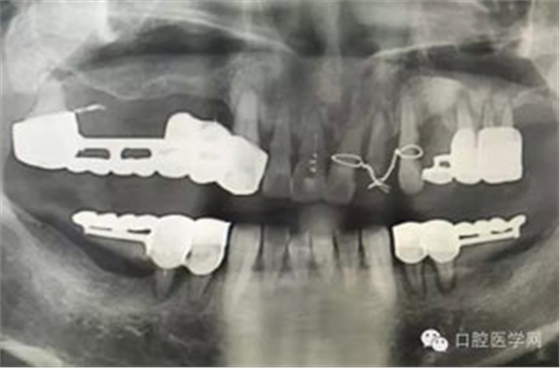

做根管的,都想做些難度大一點(diǎn)的,彎曲根管了、斷針了,可是臨床上很多時(shí)候是中等及以下難度的居多,我們要做的是盡我們所能做好這一部分,將我們力所能及的做好,而不是不切實(shí)際的幻想做一些我們條件設(shè)備不夠的病例。有些時(shí)候看到一些病例,很難想象是我們同行做的,我們是人,而不是神,我們也需要生活,我們追求效益沒(méi)有錯(cuò),我們給患者推薦好的材料,最終受益多的還是患者,這沒(méi)有錯(cuò),但是我們不是賣(mài)產(chǎn)品的,我們的本質(zhì)是醫(yī)療,不是流水線(xiàn)上的工人,將商品加工賣(mài)出去,我們所做的一切都是建立在符合修復(fù)設(shè)計(jì)原則的基礎(chǔ)上的,如若不符合,我們做的再美觀,再便宜,那又有什么意義呢?無(wú)論我們做什么樣子的修復(fù)體或者是治療,我們的標(biāo)準(zhǔn)是一致的,教科書(shū)上有明確的規(guī)定,我們這社會(huì)也有畸形,就拿簡(jiǎn)單的冠修復(fù)來(lái)說(shuō),我們花費(fèi)的精力是差不多的,我們需要的步驟是一樣的,但是價(jià)格差別那么大,是我們自己制定價(jià)格的問(wèn)題,還是社會(huì)的問(wèn)題?如若我們的冠的價(jià)格的制定差別不大,我們將更多的心思放到醫(yī)療本身上面,那么最終受益的還是患者,可是現(xiàn)在是顛倒的,我們成了產(chǎn)品的推銷(xiāo)者,整天想著怎么樣將價(jià)格高的冠賣(mài)給患者,而忽略了提高學(xué)習(xí)我們自身專(zhuān)業(yè)能力,我們整天想著怎么樣將環(huán)境打造的多么的好,然而材料上面卻是怎么樣的省怎么來(lái),什么便宜用什么,裝修上面我們可以花很多,材料我們卻很摳,有時(shí)候我們材料買(mǎi)很好,可是我們卻束之高閣,很多時(shí)候我們講理念,講概念,可是我們卻很少腳踏實(shí)地的去做我們的專(zhuān)業(yè),只是用這些新鮮的名詞去和患者溝通。給大家看幾張不良的修復(fù)設(shè)計(jì)。

病例1:患者迫切希望保留自己的這一顆牙齒,根尖周陰影比較大,二度松動(dòng).而且旁邊有種植修復(fù)體,和患者溝通好后,治療好后觀察一個(gè)月后冠修復(fù),因?yàn)橛蟹N植的后期修復(fù),所以有了機(jī)會(huì)觀察,術(shù)后三個(gè)月和術(shù)后四個(gè)月,根尖恢復(fù)的還算不錯(cuò),希望能夠繼續(xù)觀察下去.這樣子的病例,做的時(shí)候我們一定要非常的小心,和患者要有充分的溝通以及不同科室的溝通然后決定怎么樣做比較好,假如就是出現(xiàn)了問(wèn)題,到時(shí)候我們也比較好處理些,免得我們自己到時(shí)候不好收?qǐng)觥?/span> 病例2:364647中齲的樹(shù)脂充填,現(xiàn)在樹(shù)脂的充填材料非常之多,有些時(shí)候,我們感覺(jué)有了好的材料我們就可以做出好的修復(fù),可是這是在我們有扎實(shí)的基本功的基礎(chǔ)上的,我們可以沒(méi)有那么好的樹(shù)脂,那么多的顏色選擇,修復(fù)的那么的逼真,但是我們至少要恢復(fù)患者牙齒的功能,將腐質(zhì)去除干凈,薄壁弱尖消除掉,選擇好適應(yīng)癥,給患者以盡可能好的修復(fù)。 來(lái)源于KQ88